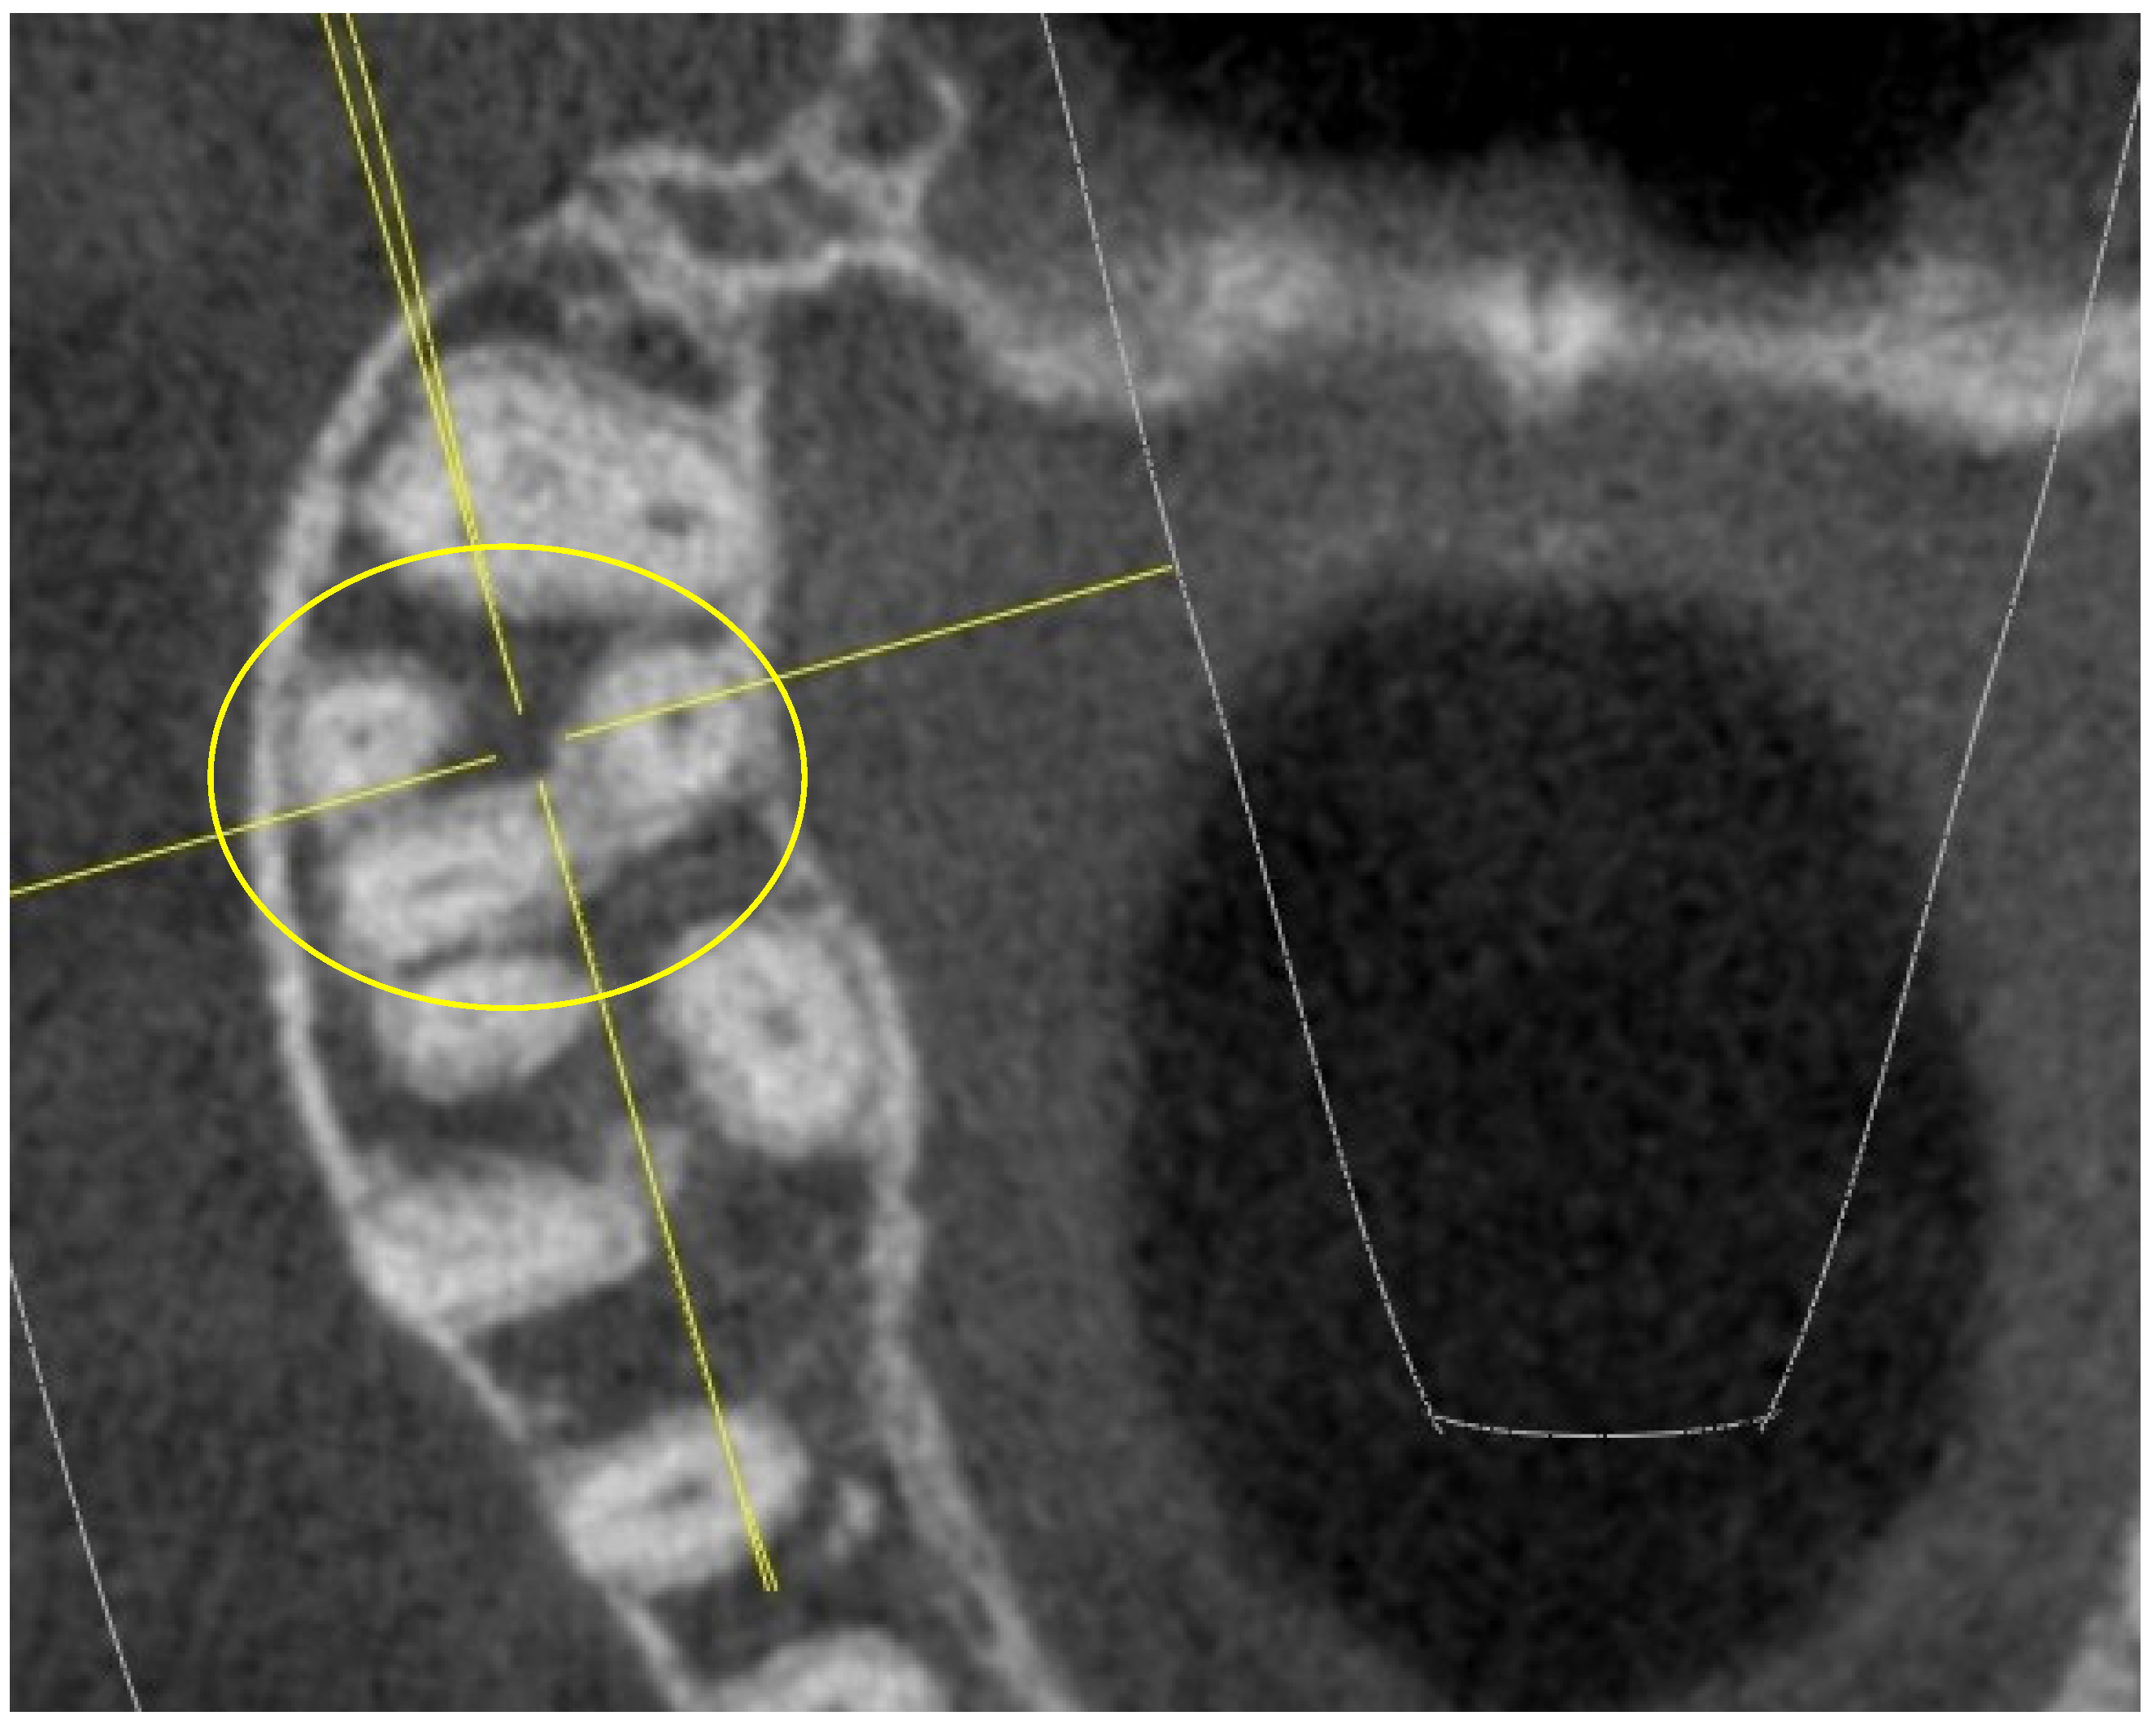

- shape of the pulp chamber associated with a letter of the alphabet (in relation to the number and arrangement of canal orifices);

- K: in maxillary molars with the presence of four canal orifices: MB, MB-2, disto-buccal and palatal; a line joining the disto-buccal and palatal and two other lines radiating from the center of this line to MB and MB-2, forming the letter “K” of the alphabet.

- Y: in maxillary molars with three canal orifices: MB, disto-buccal and palatal; when a line is formed joining the three canals in the center of the access cavity, it resembles the letter “Y” of the alphabet.